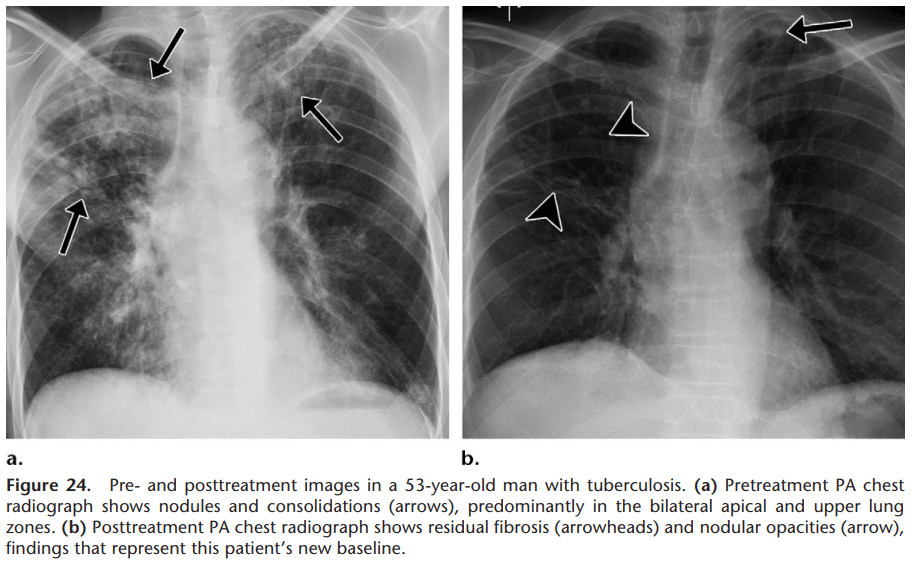

gambar radiologi tuberkulosis setelah dan sesudah pengobatan, sumber: Pulmonary Tuberculosis: Role of Radiology in Diagnosis and Management DOI: 10.1148/rg.2017160032

Foto thorak digunakan sebagai pendukung pemeriksaan dahak. Pada beberapa kasus terjadi sesak nafas dan komplikasi lainnya juga memerlukan evaluasi foto thorak